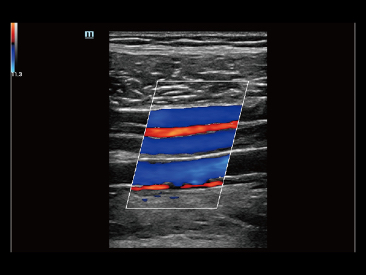

Oprócz uzyskiwania jako?ci obrazu typowego dla aparatów klasy premium, Resona 7 rozszerza mo?liwo?ci klinicznych badań USG dzi?ki rewolucyjnej funkcji V Flow, s?u??cej do oceny hemodynamiki naczyń, a tak?e najlepszej na rynku funkcji inteligentnego, automatycznego uzyskiwania p?aszczyzny na podstawie zestawów danych obj?to?ciowych 3D, umo?liwiaj?cej diagnozowanie stanu Centralnego Uk?adu Nerwowego u p?odu. Aparat Resona 7 ??czy w sobie najbardziej intuicyjn?, wielodotykow? obs?ug? za pomoc? gestów oraz wszystkie kluczowe funkcje kliniczne, co sprawia i? jest prawdziwym liderem we wprowadzaniu innowacji w ultrasonografii.